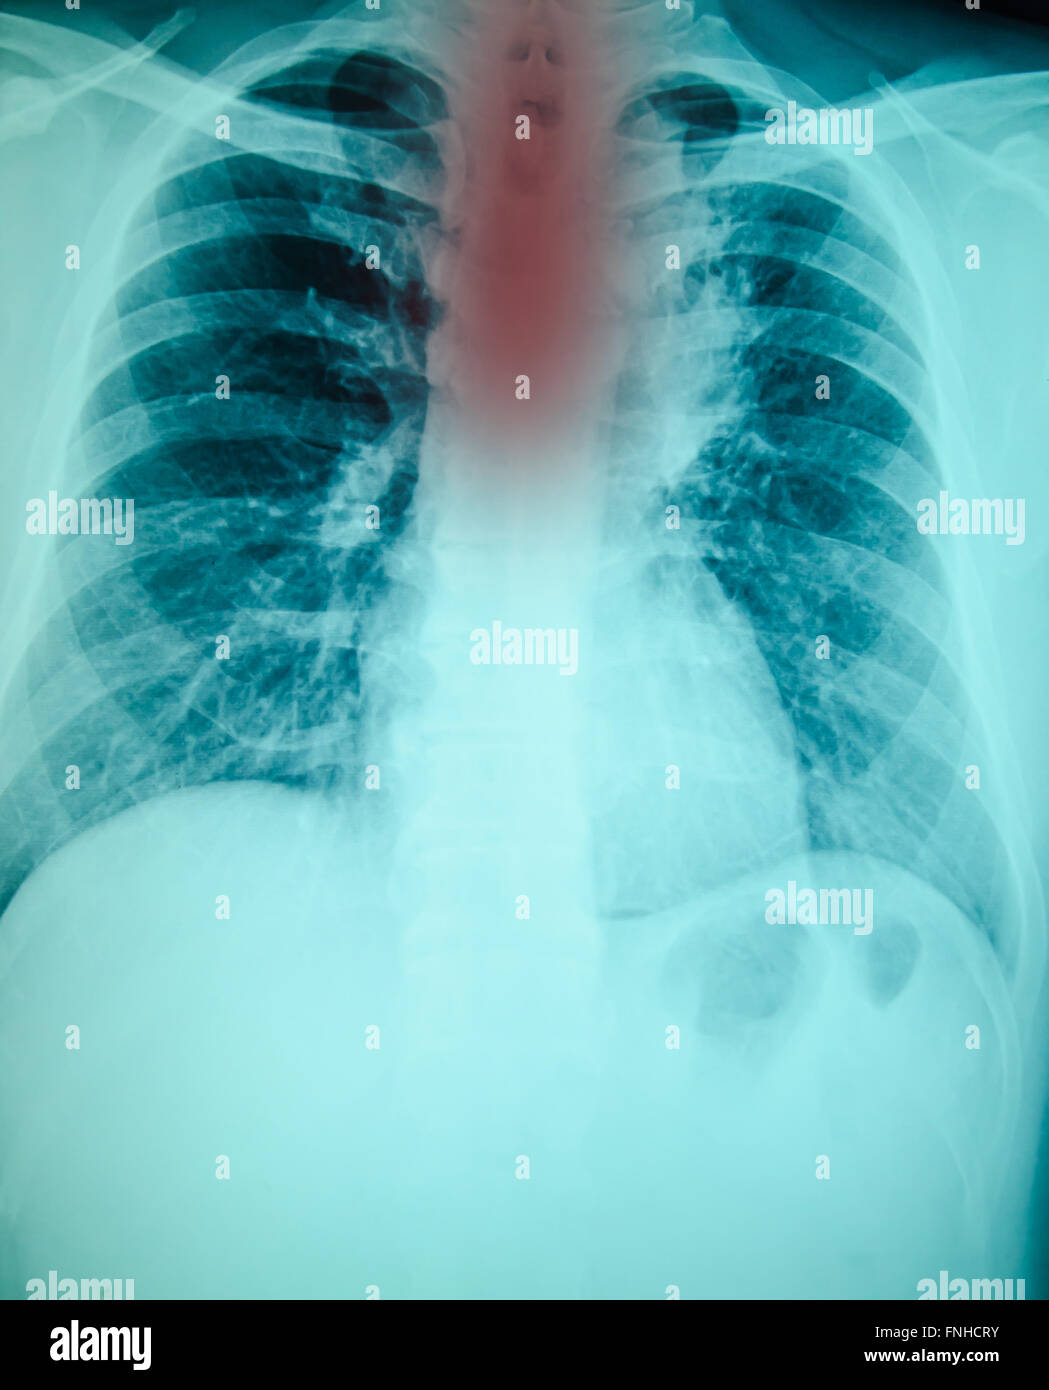

XRay Chest PA View Normal. Download Scientific Diagram What Does Chest X Ray Pa And Lateral Mean ap portable view of the chest; Two views (pa and lateral) are. Pa and lateral views of the chest; This section lists what the radiologist saw in each area. Which one is ap and which one is pa? On these chest films the heart is extremely dilated. first study the pa and lateral chest film and then continue. What Does Chest X Ray Pa And Lateral Mean.